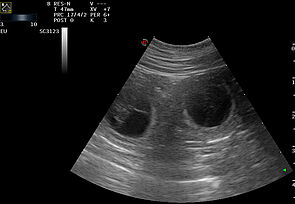

Heute haben wir die Wurmkur beim Tierarzt abgeholt und noch mal schnell einen Ultraschall gemacht. So schön zu sehen das es den kleinen gut geht und sie schon ordendlich gewachsen und entwickelt sind. Auf dem Bild kann man einen kleinen Fuß mit Krallen erkennen.

Am Vormittag hatten wir sicherheitshalber noch mal einen Ultraschall Termin, um sicher zu gehen das es den kleinen gut geht. Gott sei dank war alles in Ordnung.

Nachdem Chilly bis nachmittags immer noch keine Anzeichen der eröffnungsphase zeigte, sind wir dann am frühen Abend noch mal in die Tierarztpraxis gefahren. Dort haben wir erneut einen Ultraschall gemacht und alles war in Ordnung. Sicherheitshalber haben wir aber auch noch ein Röntgenbild gemacht darauf konnte man allerdings nur noch drei Welpen erkennen. Das war erst mal eine große Überraschung für mich, denn ich hatte mit 5-8 Welpen gerechnet. Die wurden beim ersten Ultraschall bei der Spezialistin auch gesehen und als gut befunden. Drei hatten natürlich mehr Platz im Bauch und hatten es dementsprechend natürlich auch nicht eilig. Bei den dreien waren aber die Herztöne immer noch hervorragend.